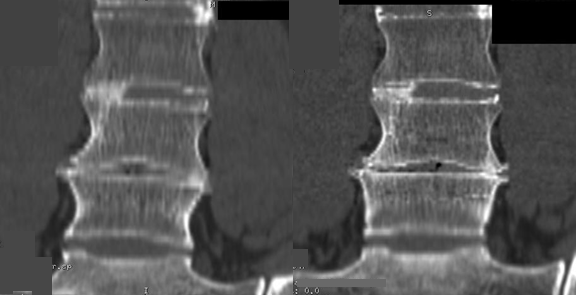

These two coronal CT Scans of the spine were performed on the same patient, same machine, same day. Clearly, on the right, there is the appearance of bone between the vertebral bodies bridging the disc space. In a fusion trial this is success but in a disc replacement trial, this is failure. However, the scan on the right was performed with incorrect technique. Correct technique performed on the left shows that there is clearly no fusion.